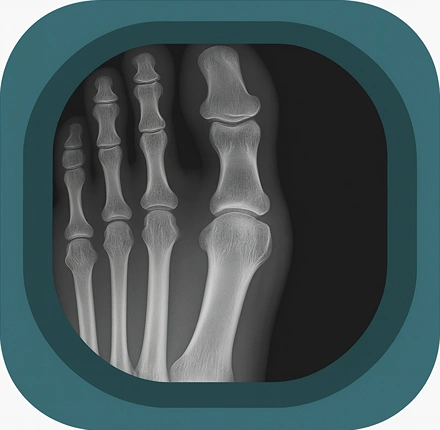

Explore high-quality X-ray anatomy from head to toe. Our database features carefully labelled images to visualize fine structures—perfect for radiologists, students, and surgeons.